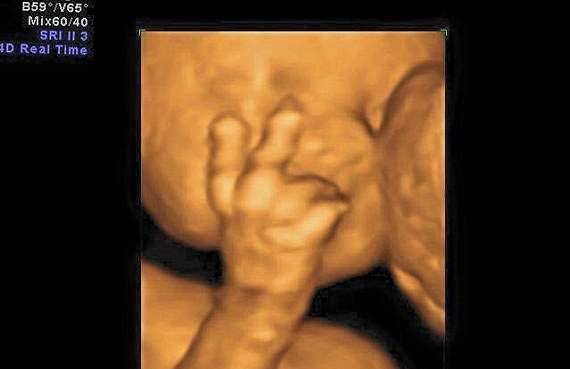

▼怀孕7个月的準妈妈去做超音波检查,发现宝宝伸出了两根手指。